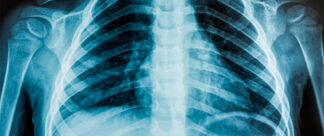

qual vacina da tuberculose